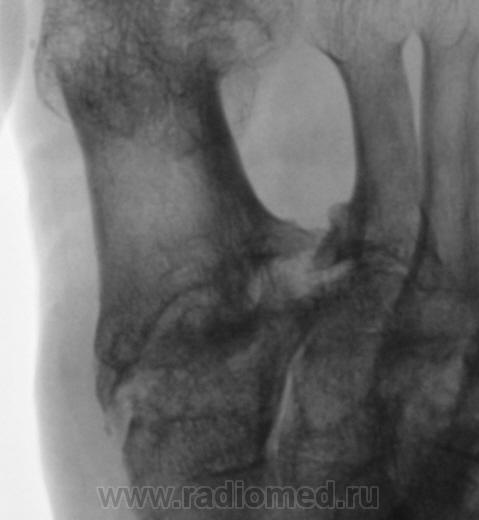

Пациентка направлена на рентгенографию стоп в прямой проекции с диагнохом - "Поперечное плоскостопие".

Произведена рентгенография обеих стоп в прямой проекции.

Думаю, что это дисхондроплазия - болезнь Олье.

Сильно сомневаюсь в болезни Олье - затронуты только суставные концы, диафизы интактны. Считаю - остеоартропатия, вероятнее всего - подагра

Классика подагры - наличие тофусов в параартикулярных мягких тканях... Механизм поражения скелета при подагре - атрофия от давления тофусами. А здесь - их совершенно не видно, мягкие ткани просто отодвинуты, но обьем то их - нормальный...

Согласен с артропатией, но подагра - сомнительно....

Поскольку артропатий великое множество....почему бы и не псориатическая...к примеру. Как там с анамнезом?

Пациентка весьма преклонного возраста - за 70 лет.